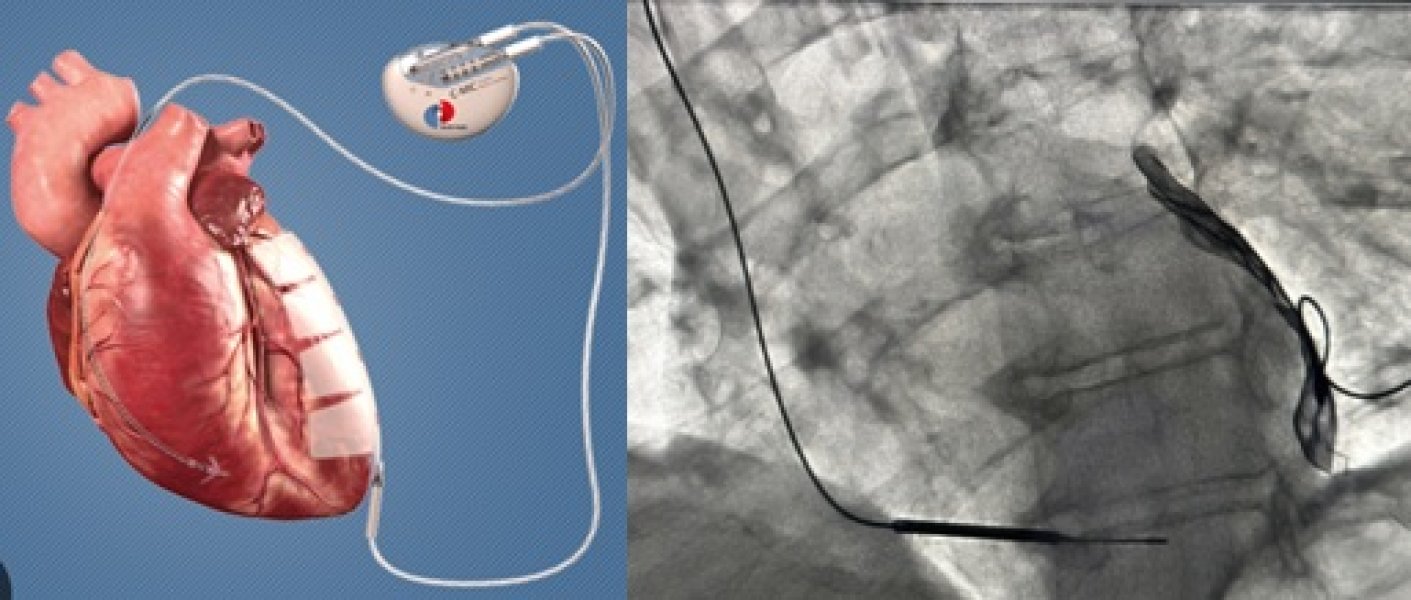

U sklopu međunarodnog projekta u Kliničkom centru Univerziteta u Sarajevu 58-godišnjem pacijentu ugrađen je uređaj za mikrostrujnu terapiju srca (Cardiac Microcurrent Therapy System C-MIC-II). Ovo je prvi put u historiji KCUS-a da je urađena ugradnja ovakvog uređaja.

Uloga ovog aparata je da kontinuiranom mikrostrujom određene frekvencije, poveća srčanu snagu i dovede do poboljšanja srčane funkcije.

Prema riječima prof. dr Nermira Granova, direktora hirurških disciplina, ugradnjom ovih uređaja bićemo u mogućnosti pomoći velikom broju pacijenata koji imaju oslabljenu snagu srca, na način da im se kroz ovu terapijsku mjeru značajno obnovi srčana snaga i oporavi srce.